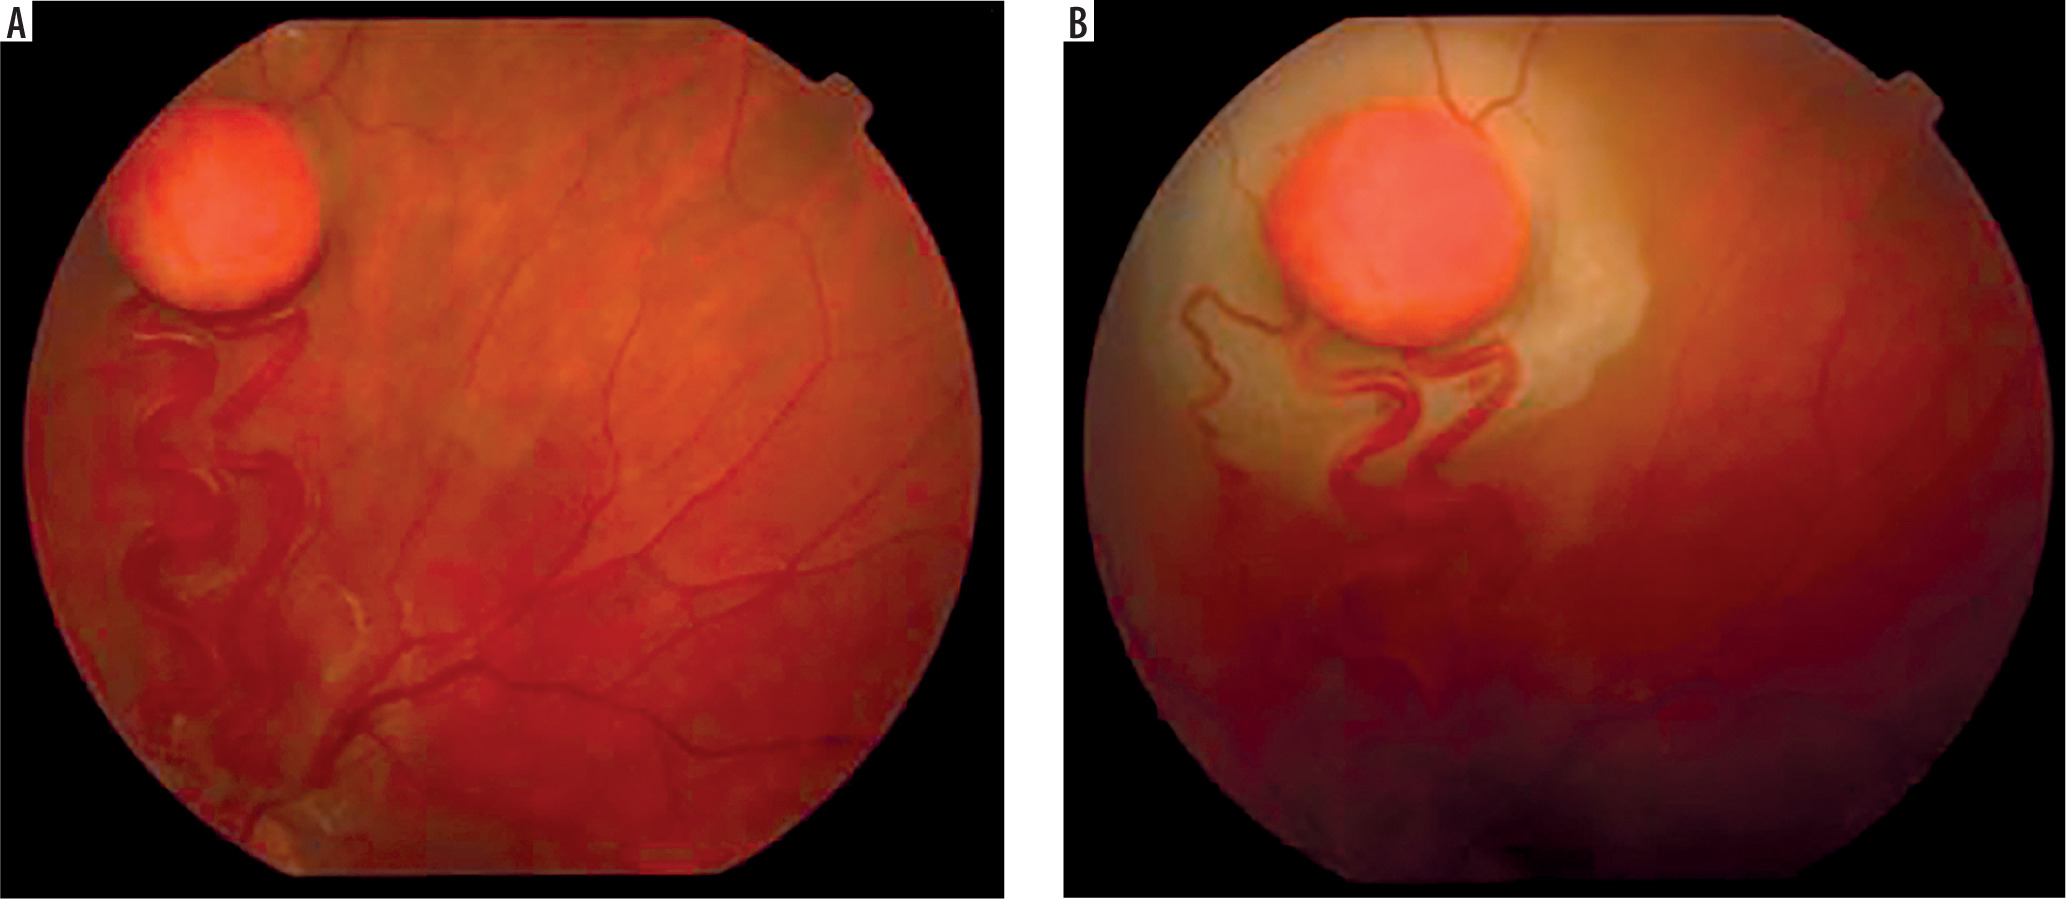

It is a very rare disease, affecting an estimated one in 30,000–40,000 individuals, with around 1,000 cases reported in Poland. The condition is inherited in an autosomal dominant manner. The syndrome is caused by constitutional mutations of the VHL tumor suppressor gene located on the short arm of chromosome 3. Constitutional mutations affecting a single gene are present in all cells of the body and represent the primary cause of pathology in this type of genetic disorder. The syndrome is characterized by the presence of hemangioblastoma-type tumors in the cerebellum, spinal cord, brain, visceral organs, and the eye [16]. The tumors consist of components of hemangioblastomas [6]. Visceral abnormalities are associated with the presence of pancreatic and renal cysts, as well as polycythemia. Tumors such as pheochromocytoma and adenocarcinoma may also occur. Hemangioblastomas that develop in the brain and spinal cord can cause headaches, vomiting, weakness, and loss of muscle coordination (ataxia). Within the ocular globe, capillary malformations affecting the optic nerve and retina are detected. The malformations appear as tumors in both eyes, located peripherally and centrally [6] (Figure 8A, B). Peripheral distribution is characterized by the presence of tortuous, dilated vessels that supply and drain blood from the tumor. In contrast, centrally located vascular tumors typically exhibit an endophytic growth pattern and lack afferent and efferent vessels associated with vascular malformations. Disease progression may lead to retinitis and retinal detachment, iridocyclitis, and rubeosis iridis. The changes may result in the development of secondary glaucoma.

Figure 8A, B

Retinal vascular malformation in von Hippel-Lindau syndrome – before treatment and during therapy